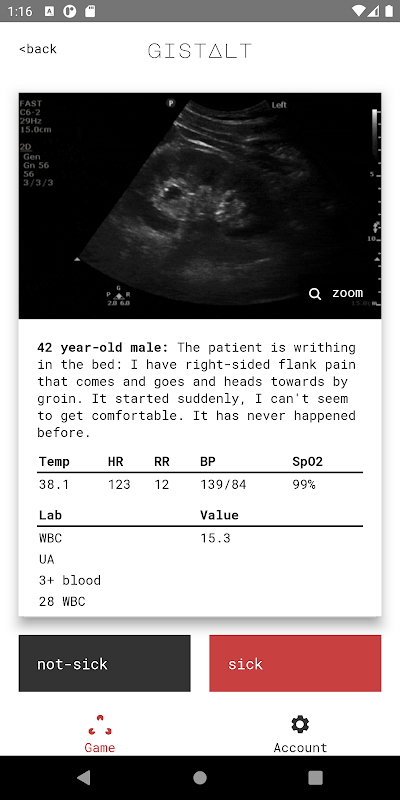

Your goal playing gistalt is to accurately identify which patients are sick (requiring hospitalization or immediate interventions for stabilization) or not-sick (conditions that can be safely treated with outpatient follow-up).

gistalt games are simple and fun. You'll start with a stack of patient presentations including vital signs, laboratory results and imaging. Swipe each card left (for not-sick) or right (for-sick) to see the next question. At the end of the stack, review your responses and see your score. Your gistalt score specially gauges your ability to detect the most critically-ill patients and institute the treatments that will make a difference.